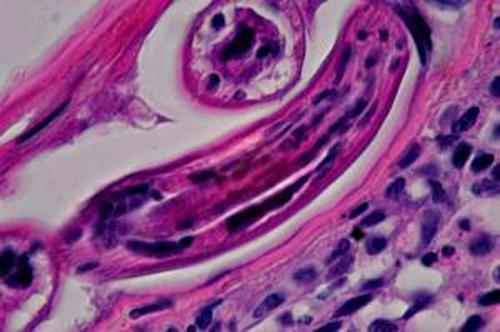

Dans le derme, on note des lésions très exsudatives et inflammatoires centrées sur les annexes folliculaires et sudorales. Il s’agit de remaniements inflammatoires à forte prédominance éosinophile avec en général obstruction des lumières annexielles par l’infiltrat (Photo 13,14,15). Ici et là, sur certaines coupes, notamment sur la réaction au PAS, on observe de petits éléments vermiformes, ronds, cylindriques non segmentés, à cuticule lisse, intraluminaux ou intra-pariétaux au sein des follicules pileux (Photo 16,17,18,19,20,21,22,23) ou des glandes sudorales apocrines épitrichiales (Photo 24 & 25), évoquant des helminthes.

Photo 18 (Hémalun Eosine X 200) peau velue : Certains éléments vermiformes sont

inclus dans de petites logettes au sein de la paroi des follicules pileux,

ici un même élément vermiforme en coupe transversale et longitudinale.

Légendes de la Photo 18 :

- Étoile rouge : lumière du follicule pileux

- Double flèche verte : GEE

- Double flèche bleue : derme inflammatoire péri-folliculaire (infiltrat riche en granulocytes éosinophiles et en palsmocytes)

- Flèches jaunes : élément vermiforme rond cylindrique non segmenté

Photo 19 (Hémalun Eosine X 400) peau velue : Vue rapprochée de la Photo 18.

Ici un même élément vermiforme en coupe transversale et longitudinale :

élément rond cylindrique non segmenté à cuticule lisse et fine.

Il semble y avoir des cellules musculaires et une cavité centrale contenant des organes.

Légendes de la Photo 19 :

- Étoile verte : “matériel organique” dans la cavité centrale

- Flèches turquoises : cellules musculaires sous-cuticulaires

- Flèches jaunes : cuticule du ver